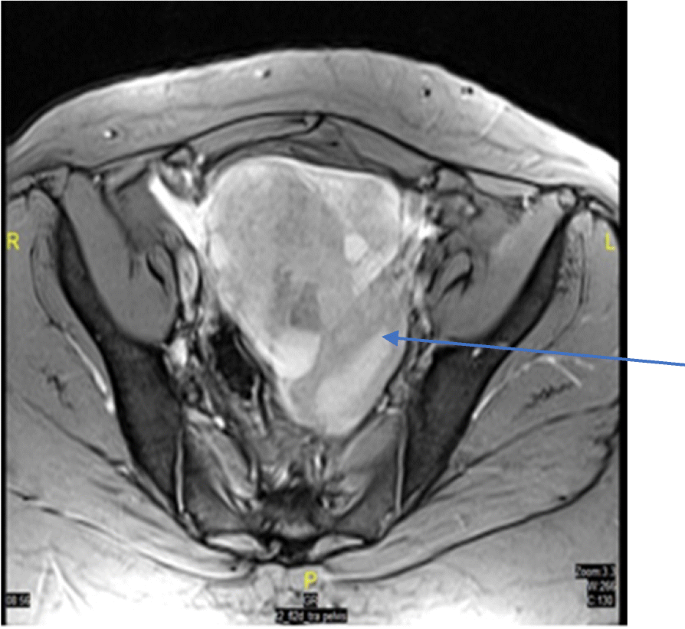

Abdominal ultrasound showed a large solid cystic mass in the right adnexa region, reaching the midline (≈6 × 13 cm) with mild vascularity in the solid component. Both ovaries were not separately visualized. There was mild left hydrosalpinx and mild ascites. Transvaginal ultrasound did not show the left ovary, but the right ovary was visualized separately (2.5 × 2.1 cm) and confirmed the presence of complex solid cystic mass in the middle of the pelvis. The mass (13.5 × 9.8 cm) extended to the left adnexa, with cystic area (9.2 × 5.9 cm) and a solid component (9.1 × 7 cm) that had increased vascularity. Further chest/abdomen/pelvis CT and MRI (Fig. 1) confirmed the size and solid/ cystic nature of the mass and showed no metastatic lesions, and also deviation of uterus to the left side.

Transverse T2 MRI section. The section shows well-defined complex lesion (arrow) with solid and cystic contents in the pelvis, extending on either side of the midline reaching to both sides of adnexa and measuring 13 × 9.4 × 8.1 cm. Ovaries are not seen separately from the lesion. Uterus shows mild deviation to the left side due to pressure effect from the mass. No obvious lymph nodes or signs of metastasis

Regarding the tumor size of MSO, a range of dimensions (0.1–4.2 cm) has been reported (Table 1), and an analysis of large series of 68 MSO patients observed a mean tumor size of 5.28 cm [8]. To the best of our knowledge, our MSO is the possibly the largest (11 cm) reported MSO with PTC tumour confirmed by histopathology to date. Others found a MSO measuring 20 cm, but did not report the tumor histopathology; hence we are unable to judge their tumor subtype [8]. Our MSO is also first to be reported from the Middle East and North Africa region. Such a large sized tumor is likely to cause pressure effects (as observed in our patient who had deviation of uterus to the left side) (Fig. 1).